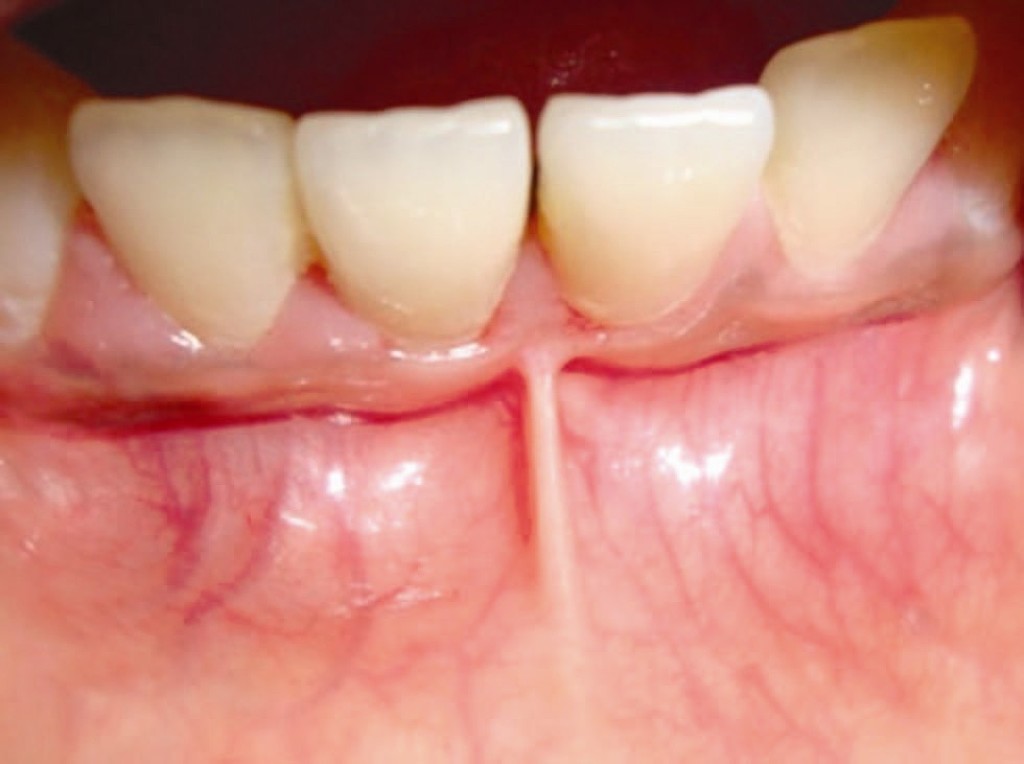

Frenulum In The Mouth

What Is A Frenum (Frenulum)?

In our mouth, most people have two groups of tissue called frenums found in and around the gums and teeth. It is a piece of really soft tissue that appears as a thin line between the gums and lips. You can find it on the top and the bottom of your oral cavity. There’s also a frenum that extends along the bottom of the tongue and connects to the bottom of the mouth just behind the teeth. Different people have different frenums. It can vary in length and thickness.

Occasionally a frenum can get stretched or torn from kissing, eating, or wearing oral appliances like braces. Although this type of injury may bleed a lot, normally there’s no need for stitching or other serious medical procedure. Nevertheless, some dentists suggest treating a person with a cut frenum for indications of physical, cause this type of injury can often be a sign of abuse.

If your frenum tears constantly this may be painful and annoying so your dentist or oral surgeon may advise surgical removal. This type of operation is called a frenectomy. If you experience persistent problems with your frenulum mouth, teeth and gums may suffer severely if not treated properly.

Labial frenum – This type of frenum is placed in the front of your mouth between the upper lip and gum. His counterpart is positioned between the lower gum and the lower lip. If there is an issue with this type of frenum, it can change the way your teeth grow in and can influence your dental health. Particularly it can pull your gums away from a tooth revealing the root.

Lingual frenum – This type of frenum is located between the floor of your mouth and the base of your tongue. It comes in different sizes and sometimes it can limit the movement of your tongue. This means frenum is tight, and we call this condition: tongue-tie. If this happens, it can affect the way the tongue moves in your mouth. This problem is especially annoying for babies because it makes it hard for a baby to feed properly.

Possible Problems With Frenum

The main purpose of a frenum is to give the lower and upper lip, as well as the tongue proper support and more stability in your mouth. If you suffer from an oversized frenum, it can lead to various problems that can affect your teeth, gums, and mouth.

· disruption of the healthy growth of your upper two front teeth, which may cause a gap

· the gap formed between front teeth

· receding of gum tissue away from the root of the teeth and revealing the tooth root.